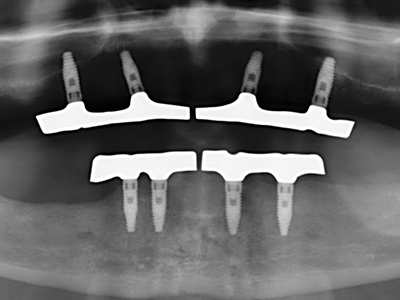

Индикация: Възстановяване на кост

Автогенни костни присадки се използват под формата на блокчета, миди, пръстени и се комбинират с костозаместителни материали като стърготини. Ако имплантното ложе се обработва едновременно с аугментацията, различни системи за филтриране на кост са доказали своята ефективност за събиране на получените костни стърготини. В алтернатива, имплантното ложе може да бъде подготвено с апарат с ниски обороти без охлаждане. Ако не се постави имплант, костните стърготини от периферията могат да бъдат събрани с канюла за събиране на костен материал. Това също е възможно с пиезохирургия, използвайки специални накрайници, които събират костни стърготини с високо качество, в сравнение с костните стърготини, събрани с кръгли борери, както бе потвърдено в научно изследване, сравняващо двата метода (Chiriac, Herten et al. 2005).

Пиезохирургията има допълнителни предимства при събиране на костни блокове. В допълнение към високата прецизност при остеотомията, описана по-горе, употребата на фините режещи накрайници значително намаляват загубата на материал. Голяма загуба на материал по време на събиране може да се очаква с дебелите накрайници, особено при употреба на борери Линдеман (Lakshmiganthan, Gokulanathan et al. 2012). Базалното разделяне, което е необходимо, особено за присадка на блок при ретромолар, е улеснено от специално създадени правоъгълни триони. В резултат на това, пиезохирургията е разглеждана като прецизна, улеснена и безопасна процедура за събиране на костни блокове в ретромоларното пространство (Happe 2007) (Фиг. 1-12).